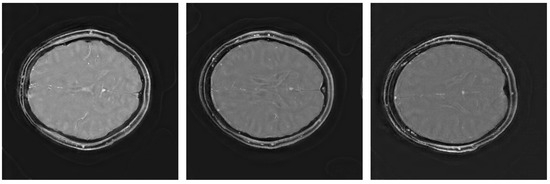

3. Results

3.1. Image Scores